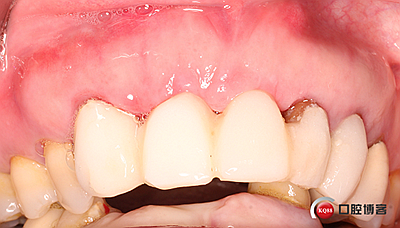

全瓷冠制作完成,齦乳頭預(yù)留空間不足,修整三角間隙。

戴牙。

戴牙后半年復(fù)查。